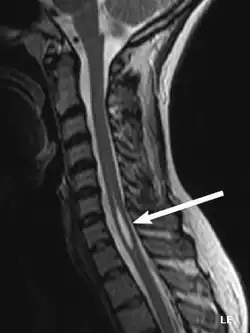

An idiopathic syrinx

Physicians now use magnetic resonance imaging (MRI) to diagnose syringomyelia. The MRI radiographer takes images of body anatomy, such as the brain and spinal cord, in vivid detail. This test will show the syrinx in the spine or any other conditions, such as the presence of a tumor. MRI is safe, painless, and informative and has greatly improved the diagnosis of syringomyelia.[18]